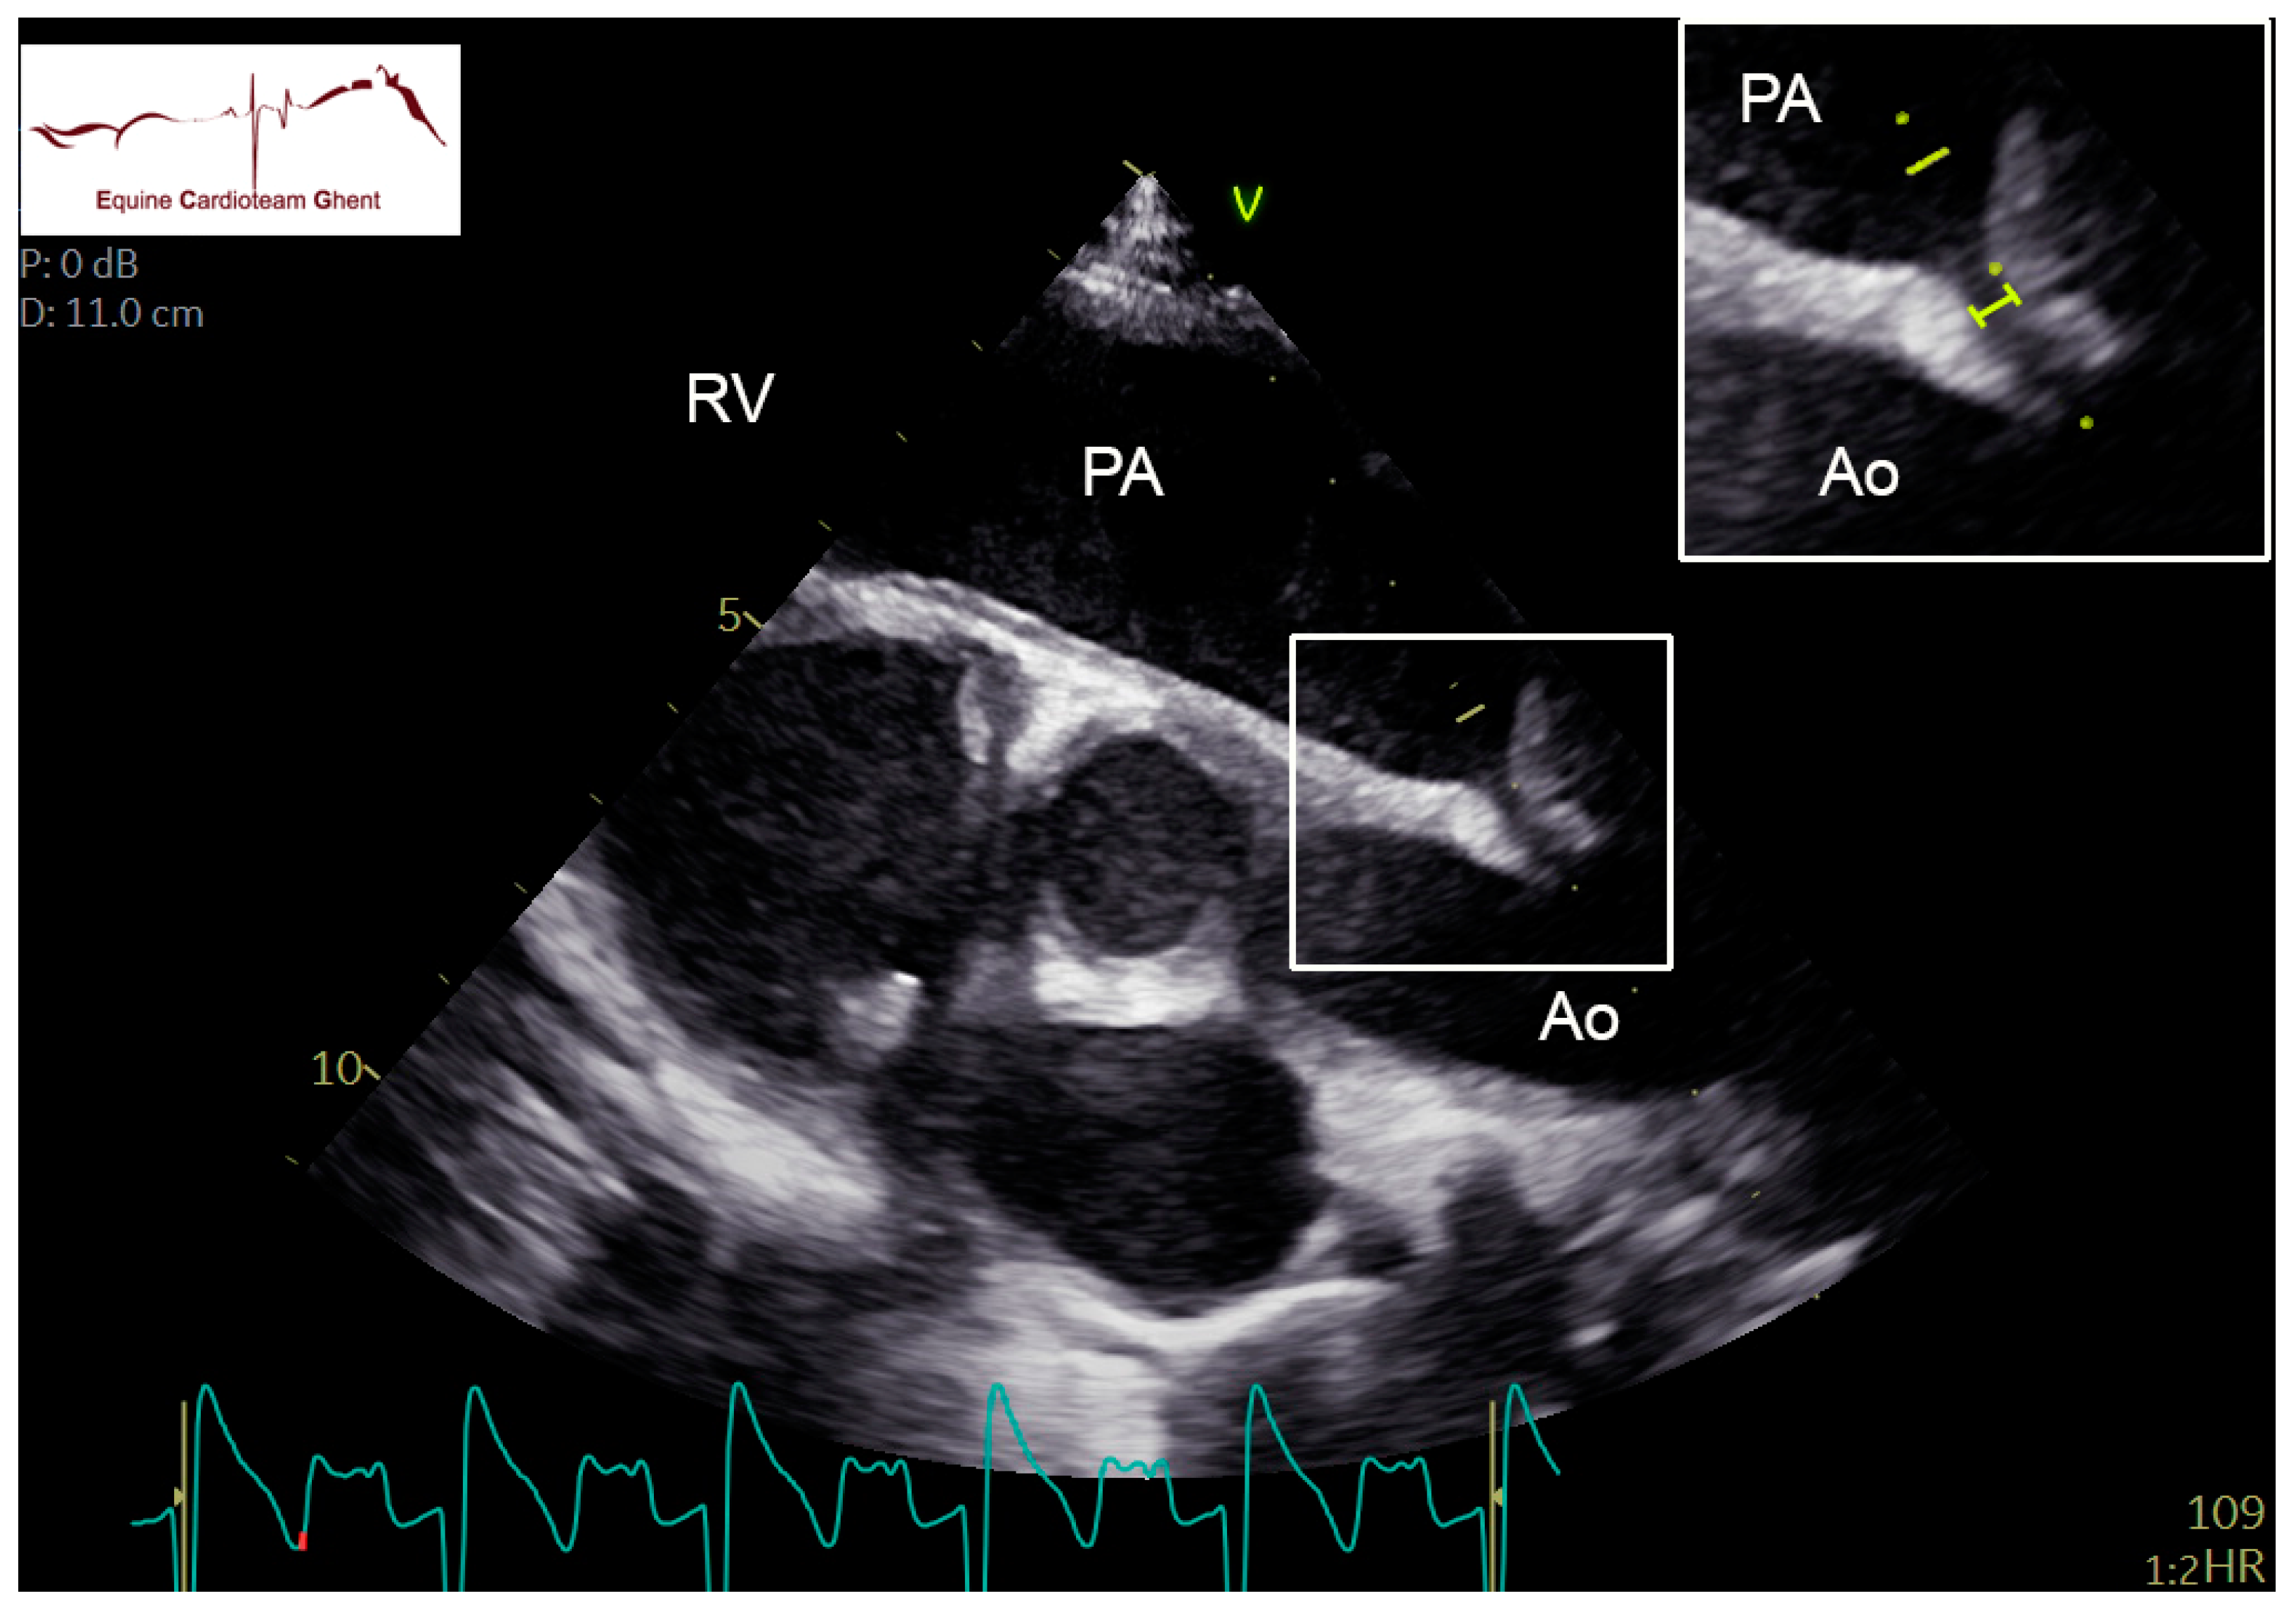

2.2. Echocardiography and Flow Doppler Examination

4. Discussion